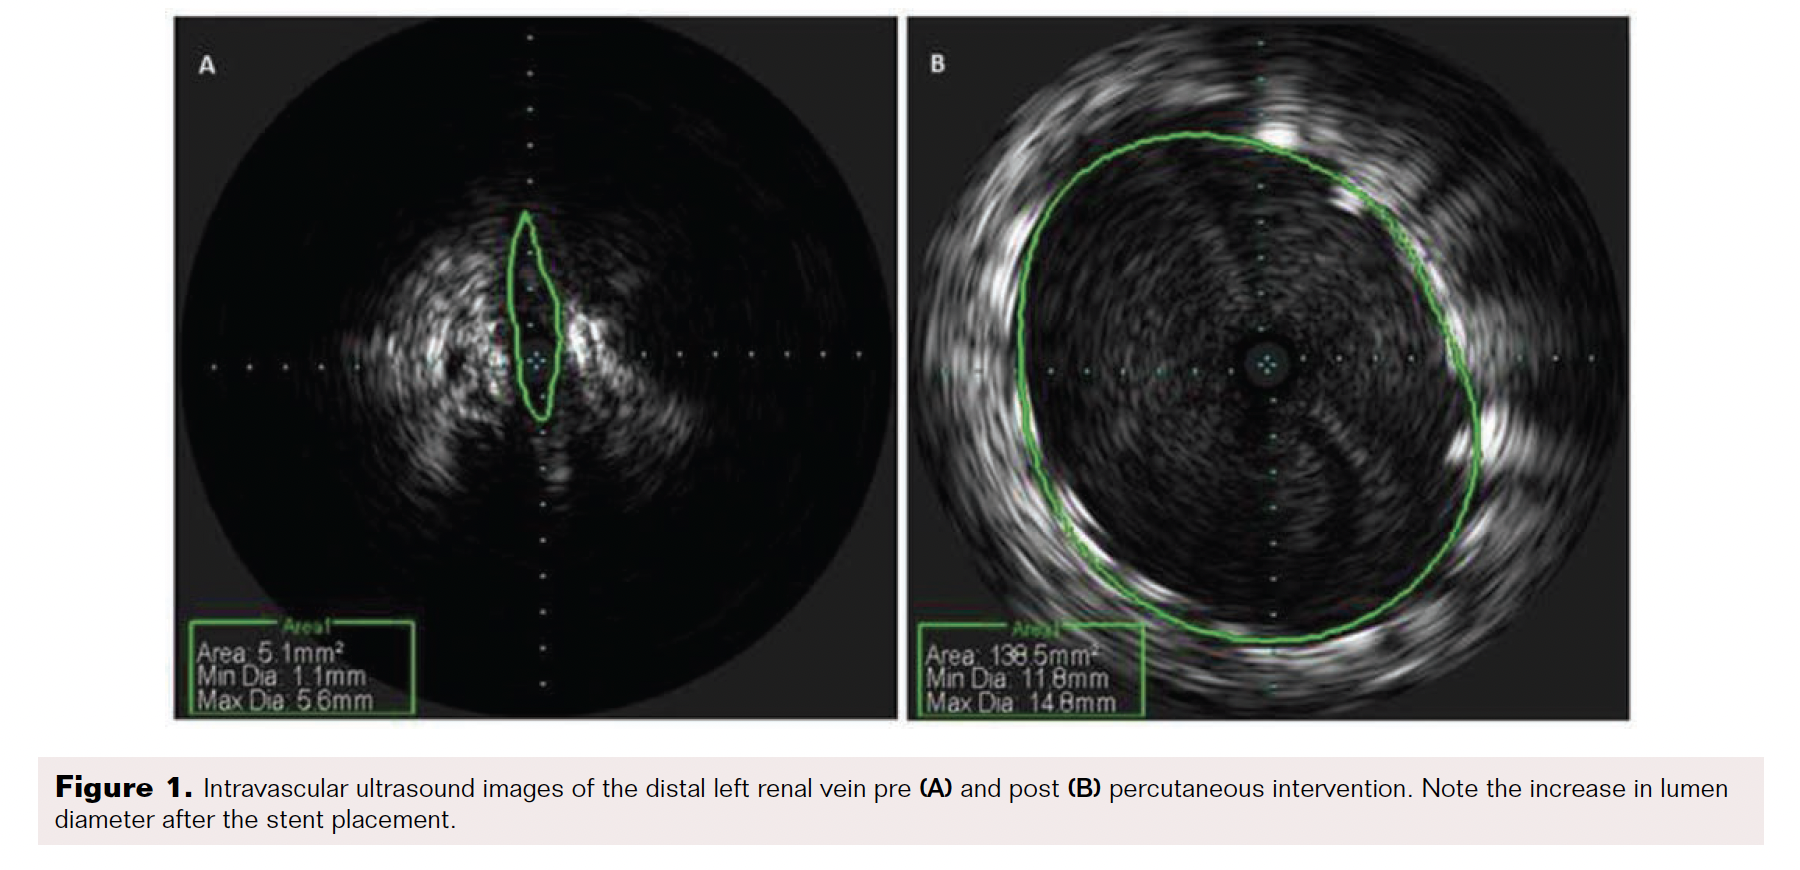

From www.hmpgloballearningnetwork.com

Nutcracker Syndrome A Rare Etiology of PCS VDM Nutcracker Syndrome Left Untreated nutcracker phenomenon is a vascular condition where there is compression of the left renal vein most commonly between. left renal vein (lrv) compression resulting in signs and symptoms is commonly known as nutcracker syndrome. the term of nutcracker phenomenon describes the entrapment of the left renal vein (lrv) between the superior. nutcracker syndrome (ns) is a. Nutcracker Syndrome Left Untreated.